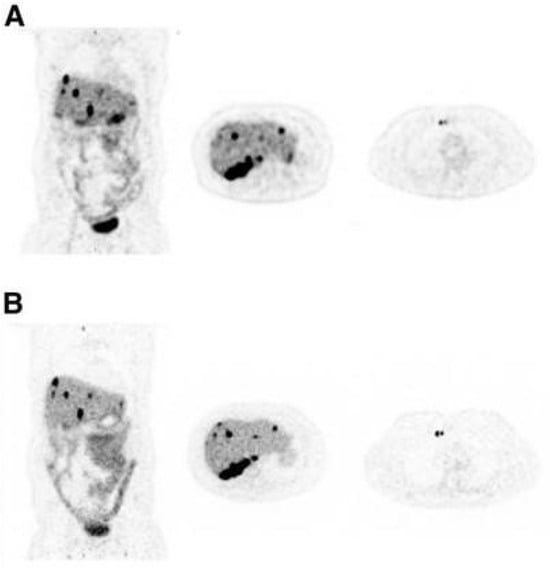

- Van Sluis, J.; Borra, R.; Tsoumpas, C.; van Snick, J.H.; Roya, M.; Ten Hove, D.; Brouwers, A.H.; Lammertsma, A.A.; Noordzij, W.; Dierckx, R.; et al. Extending the clinical capabilities of short- and long-lived positron-emitting radionuclides through high sensitivity PET/CT. Cancer Imaging 2022, 22, 69. [Google Scholar] [CrossRef]